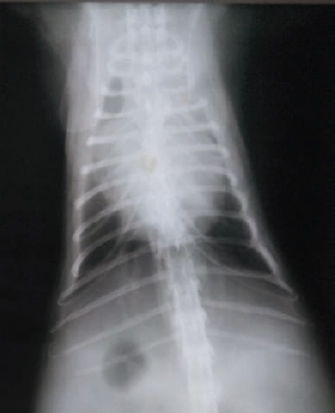

Upon radiographic examination of the hind limbs, pelvis, and spines, no abnormalities were detected within the musculoskeletal system. Lateral thoracic radiography revealed cardiomegaly in five cats (33.3%) and mild pleural effusion and vascular pattern of the lung in six cats (40%). Ventrodorsal thoracic radiographs revealed a characteristic Valentine’s heart shape in four cats (26.7%) (Fig. 1).

Fig. 1. An 8-year-old Siamese cat with FATE and HCM: Ventrodorsal thoracic radiograph showing severe cardiomegaly and a characteristic Valentine’s heart shape.

Thoracic radiographs of five cats with FATE revealed characteristic changes in the cardiac size and shape. Similar findings were previously recorded, particularly in the late stages of HCM (Trehiou-Sechi et al., 2012). Therefore, the authors recommend thoracic radiography during diagnosis of FATE. Also, it was noted that the cats with HCM were admitted within 6 hours from the onset of clinical signs because the owners had increased knowledge about what signs and risk to watch for.